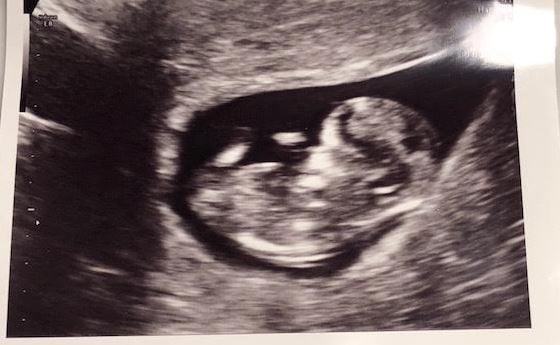

Finally have an us to share! LO is doing great at 12w3d NT scan (although they were very uncooperative in terms of getting into position!) Got to hear the heartbeat for the first time too. Feeling very relieved, especially after some spotting a few weeks ago. Love this pic because I think it looks like the baby's laughing.